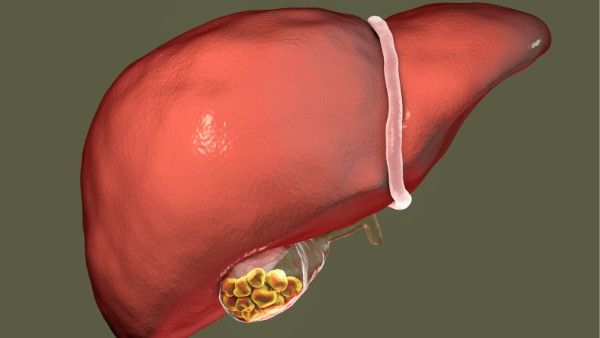

Understanding Gall Bladder Stones

Gallstones, also known as gall bladder stones or cholelithiasis, are hardened deposits of digestive fluid that can form in the gall bladder. The gall bladder is a small, pear-shaped organ located just beneath the liver. Its main function is to store and concentrate bile, a digestive fluid produced by the liver. When the bile contains too much cholesterol or bilirubin, it can form hard, crystalline particles that can vary in size from a grain of sand to a golf ball. Gallstones are a common condition and may not cause any symptoms for years, but when they block a bile duct, they can lead to severe pain and serious complications.

Cholesterol Gallstones: These are the most common type and are typically yellow-green in color. They are composed mainly of hardened cholesterol.

Pigment Gallstones: These are small, dark stones made of bilirubin. They are more common in people with certain medical conditions, such as liver cirrhosis, biliary tract infections, or inherited blood disorders.